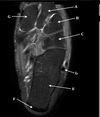

10

Q

What is letter D?

A

GLENOID

How well did you know this?

1

Not at all

2

3

4

5

Perfectly

11

What is letter A?

ANTERIOR LABRUM